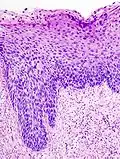

Los cambios microscópicos iniciales que corresponden al desarrollo de una neoplasia cervical intraepitelial son las displasias del epitelio, es decir, la superficie que recubre el cuello uterino, lo cual es indetectable y asintomático en la mujer.[2]

Los NIC tienen tres grados distintivos, basados en el espesor de la invasión por parte de las células escamosas:

- NIC1 (Grado I), es el tipo de menor riesgo, representa sólo una displasia leve o crecimiento celular anormal[1] y es considerado una lesión escamosa intraepitelial de bajo grado.[3] Se caracteriza por estar confinado al 1/3 basal del epitelio cervical.

- NIC2 (Grado II), es considerado una lesión escamosa intraepitelial de alto grado[3] y representan una displasia moderada, confinada a los 2/3 basales del epitelio cervical.

- NIC3 (Grado III): en este tipo de lesión, considerada también de alto grado, la displasia es severa y cubre más de los 2/3 de todo el epitelio cervical, en algunos casos incluyendo todo el grosor del revestimiento cervical. Esta lesión es considerada como un carcinoma in situ.